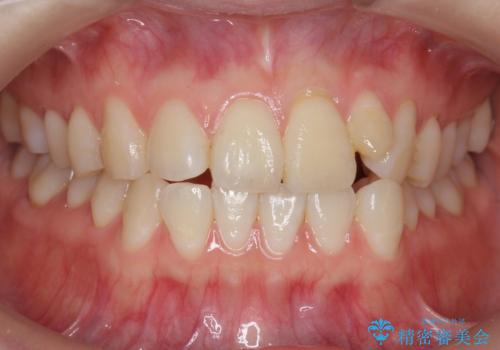

前歯が気になる 大人のマウスピース矯正 矮小歯を整える

- 前歯の並びを主訴に来院。

マウスピースで歯を抜かずに治療しています。

左上の前歯が飛び出しており、唇が笑った時に引っかかっていたのが解消しています。

左上の前歯は小さいため、(矮小歯)左右対称になるようにセラミックで形を修正する治療も併用しています。